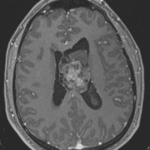

- Mildly FLAIR hyperintense intraventricular mass in the body of the left lateral ventricle measuring 4.3 x 3.7 cm in axial dimensions with heterogeneous corresponding enhancement and restricted diffusion

- The mass broadly contacts the septum pellucidum

- Associated mass effect with 1.5 cm left-to-right midline shift

- Crowding of the foramen of Monro with enlargement of the left greater than right lateral ventricles, consistent with obstructive hydrocephalus

- T1 isointense, FLAIR hyperintense material alongside the mass and layering in the left greater than right lateral ventricles and third ventricle, most likely representing hemorrhage (likely related to ventricular drain placement)

- Left frontal approach external ventricular drain terminates alongside or within the intraventricular mass. Mild edema along the parenchymal course of the catheter

Central neurocytoma